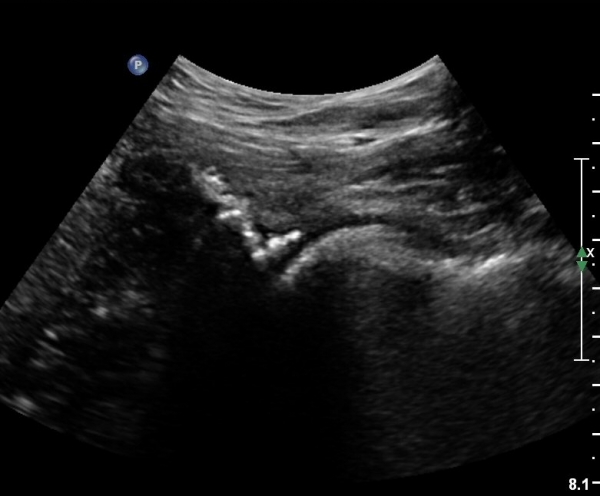

[¾ûµ¢ÀÌ] ¾ûµ¢ÀÌ °üÀý¼ø ÆÄ¿­ÀÇ ÃÊÀ½ÆÄ°Ë»ç(ultrasonography of labrum tear of hip joint)

ÃÊÀ½ÆÄ °Ë»ç

Sonography of the Acetabular Labrum Visualization of Labral Injuries During Intra-Articular Injections

What is the role of clinical tests and ultrasound in acetabular labral tear diagnostics?

Sonographic evaluation of anterosuperior hip labral tears with magnetic resonance arthrographic and surgical correlation.